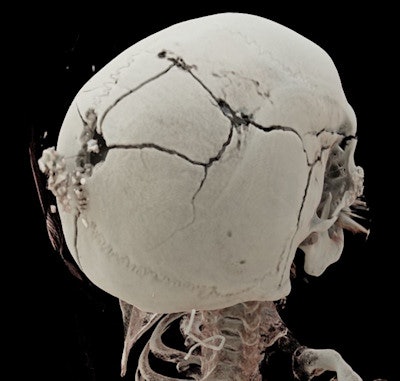

Working in a legal setting comes with specific rules and guidelines, noted Dr. Rick R. van Rijn, pediatric radiologist and chair of forensic radiology at the Emma Children's Hospital at the Academic Medical Center in Amsterdam.

"First, everything should be kept confidential, and all documents and images should be accounted for, including a record of who has access to them in order to preserve the chain of evidence," he stated. "Second, reporting has to be adapted in order to make the radiology report accessible to lay people, which requires a completely different skill set to clinical radiology."

He also suggested forensic pediatric radiology might not appeal to everybody.

"The radiologist must be willing to act in court as an expert. Sentiments can be very strong, especially in cases of abusive head trauma," he said.